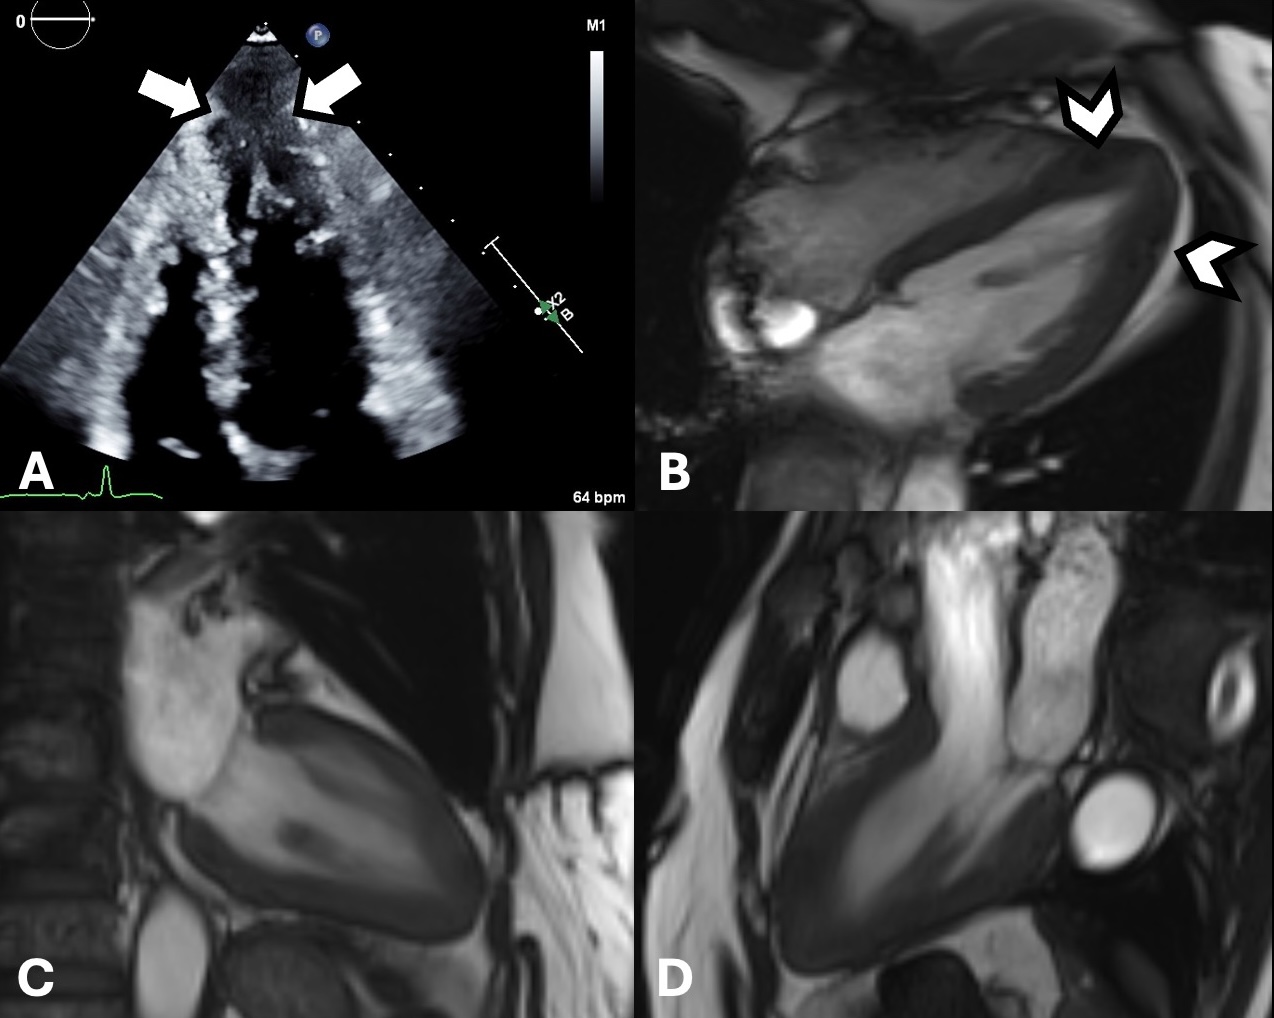

Left to right: Short-axis T1 map images from base to apex show similar distribution of elevated map values following LGE. Quantitatively, elevation of native T1 map values ranged from 1293 to 1442 ms at 3T. .jpg)